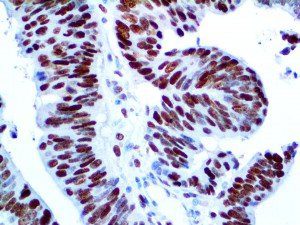

It is the ICU physician who is most likely to witness one of the deadliest manifestations of the abnormal immunological response, the cytokine storm syndrome (CSS). This response is also referred to by some as the cytokine release syndrome (CRS). CSS is characterized by continuous activation and expansion of macrophage and lymphocyte populations, which secrete large amounts of cytokines, causing the cytokine storm. This massive cytokine release is akin to hemophagocytic lymphohistiocytosis (HLH) disease, a syndrome characterized by initial unchecked and persistent activation of cytotoxic T lymphocytes and NK cells.

Clinical and laboratory manifestations of HLH include fever, enlarged liver and/or spleen, neurologic dysfunction, coagulopathy, liver dysfunction, cytopenias (i.e., low levels of erythrocytes, leukocytes, and/or platelets), hypertriglyceridemia, hyperferritinemia, hemophagocytosis, and eventually diminished NK cell activity as the immune system becomes progressively paralyzed. HLH can be familial (primary HLH) or secondary to another disease process (sHLH), such as rheumatic disease, in which it is referred to as macrophage activation syndrome (MAS, characterized by elevated ferritin).